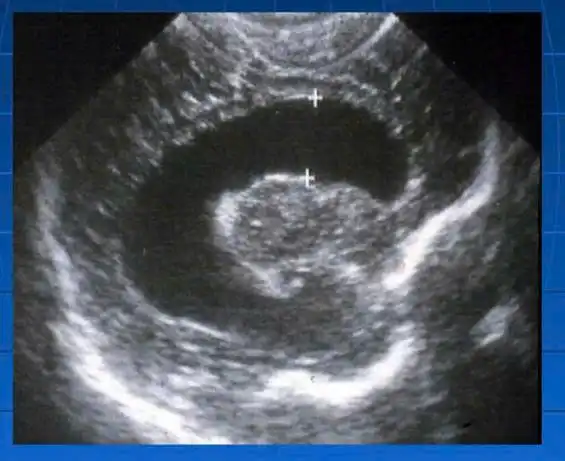

Một số hình ảnh tổn thương não phát hiện qua siêu âm thóp